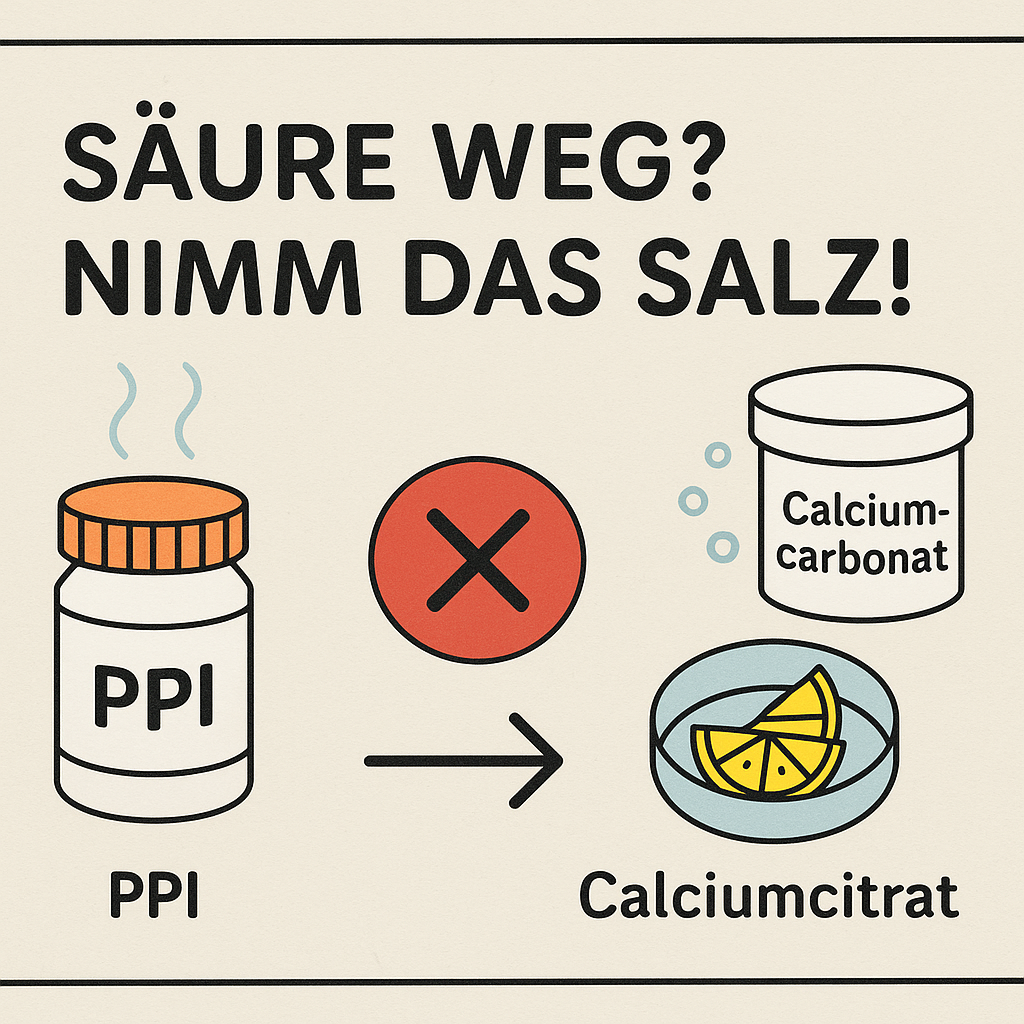

- Prompt: Ich kann mir nicht merken, dass Ca-Citrat bei gleichzeitiger PPI-Einnahme besser wirkt als Carbonat. Bitte auch visuelle Eselsbrücke.

- Antwort: SÄURE WEG? NIMM DAS SALZ! (Merksatz)

- Kurz erklärt:

- PPI → weniger Magensäure

- Calciumcarbonat braucht Säure → wirkt schlechter

- Calciumcitrat braucht keine Säure → funktioniert trotzdem

- Eselsbrücke: „Citra“ klingt wie Zitronensaft – sauer von Natur aus, löst sich auch ohne Magensäure.

- Zusammenfassung: PPI hemmt Magensäure → Calciumcarbonat unwirksam → Calciumcitrat bevorzugen.

- Kurz erklärt: